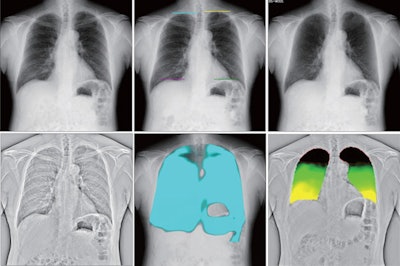

DCR is a novel real-time digital imaging technique that produces clear, wide field-of-view diagnostic images of the thorax and diaphragm in motion, as well as metrics of moving structures within the thoracic cavity. Another one of its benefits is that it requires less radiation exposure than standard CT imaging.

Dynamic image data were acquired at 15 frames per second and were synchronized with pulsed x-ray, with a radiation dose of approximately 1.7 mGy (under the 1.9 mGy dose limit for 2-directional chest x-rays recommended by the International Atomic Energy Agency, the authors noted).